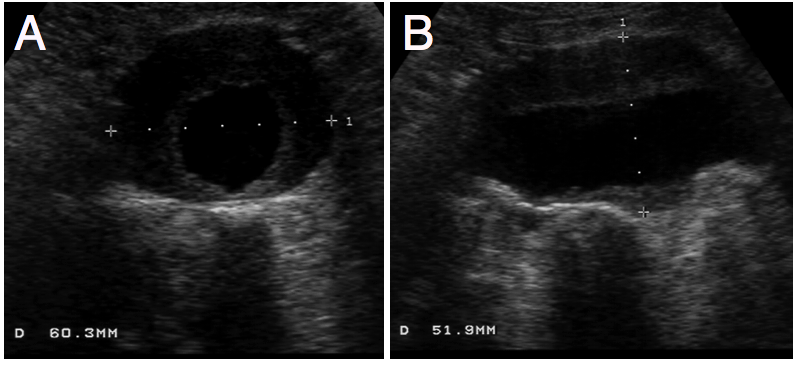

Pancreatic Psydocyst

Spherical fluid collection of pancreatic enzymes that arise from inflamatory, necrotic and hemorrhage processes of the pancrreas

persistently elevated amylase and lipase

Pancreatic Psydocyst

Spherical fluid collection of pancreatic enzymes that arise from inflamatory, necrotic and hemorrhage processes of the pancrreas

persistently elevated amylase and lipase

Pancreatic Psydocyst

Spherical fluid collection of pancreatic enzymes that arise from inflamatory, necrotic and hemorrhage processes of the pancrreas